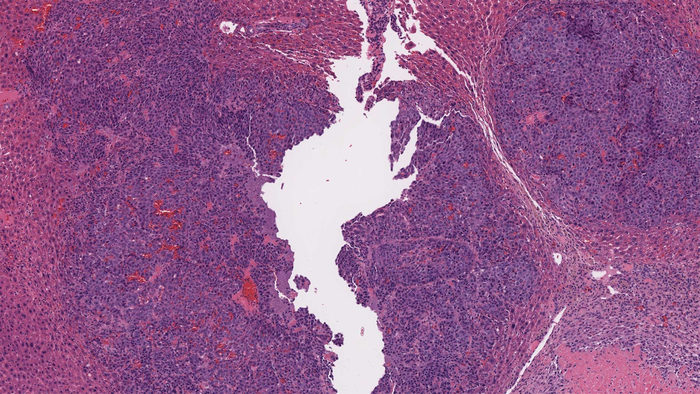

A cross-section of mouse liver tissue containing a liver cancer tumor. Cancer tissue is shown in purple and healthy tissue is shown in pink. CSHL Professor Adrian Krainer and his team found a way to make mouse liver cells produce a cancer-suppressing protein and simultaneously reduce the levels of a cancer-promoting protein, using RNA-based molecules called antisense oligonucleotides (ASOs).

Dillon Voss/Krainer lab/CSHL, 2021